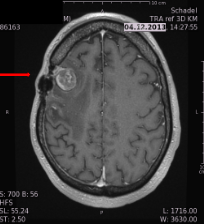

we treat the brain tumor using the latest technologies. Our efforts have saved many lifes and looking forward for many more